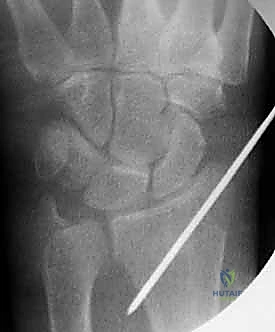

| التثبيت بالأسلاك المعدنية (K-Wires) | إجراء طفيف التوغل يتم فيه إدخال أسلاك معدنية رفيعة عبر الجلد لتثبيت العظام المكسورة بعد ردها. | الكسور المنزاحة القابلة للرد المغلق، كسور الأطفال، الكسور خارج المفصل، المرضى ذوي العظام الجيدة. | شقوق جراحية صغيرة جداً (أو معدومة)، ألم أقل بعد العملية، إزالة الأسلاك بسهولة لاحقاً بالعيادة. | خطر بسيط لالتهاب مسار السلك، قد تتطلب جبساً إضافياً للحماية، غير مناسبة للكسور شديدة التفتت. |

4. إدخال الأسلاك المعدنية (Pinning)

باستخدام مثقاب جراحي كهربائي دقيق، يقوم الدكتور هطيف بإدخال السلك المعدني الأول عبر الجلد، مروراً بالعظم السليم، ثم يعبر خط الكسر ليصل إلى الشظية المكسورة ويثبتها.

هناك عدة تقنيات هندسية لإدخال الأسلاك، أشهرها:

* التثبيت المتقاطع (Cross-Pinning): إدخال سلكين من زوايا مختلفة ليتقاطعا داخل العظم، مما يوفر ثباتاً دورانياً ممتازاً.

* تقنية كابانجي (Kapandji Technique): إدخال الأسلاك مباشرة في خط الكسر واستخدامها كرافعات لرفع العظم المنخسف ثم دفعها في العظم المقابل لتثبيته. يتميز الدكتور هطيف ببراعة فائقة في تطبيق هذه التقنية المعقدة.